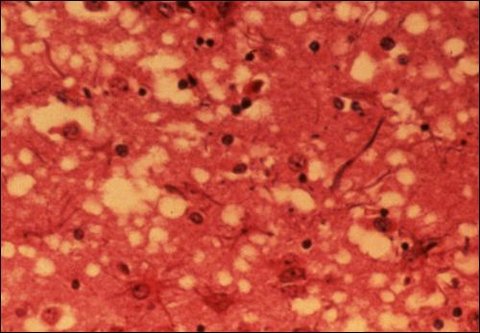

옆의 사진을 보시면 광우병에 걸린 소의 뇌사진입니다. 이렇게 광우병에 걸린 소를 인간이 먹으면 우리도 광우병에 걸리게 됩니다. 인간도 광우병에 걸리면 뇌에 저렇게 구멍이 나는거죠. 저렇게 뇌에 구멍이 생기면 어떻게 될까요 ? 공격적 성향, 무감동증 등의 정신적인 증상이 먼저 나타난다고 합니다. 이어서 기억장애 감각장애, 무언증 인지장애 등이 나타난다고 합니다. 이것은 치매와 비슷하죠. 그리고 이 광우병은 치료방법도 없습니다. 치료방법은 커녕 광우병의 원인인 프라이온이란 것은 200도의 고온에서도 죽지 않는 다고 하죠.